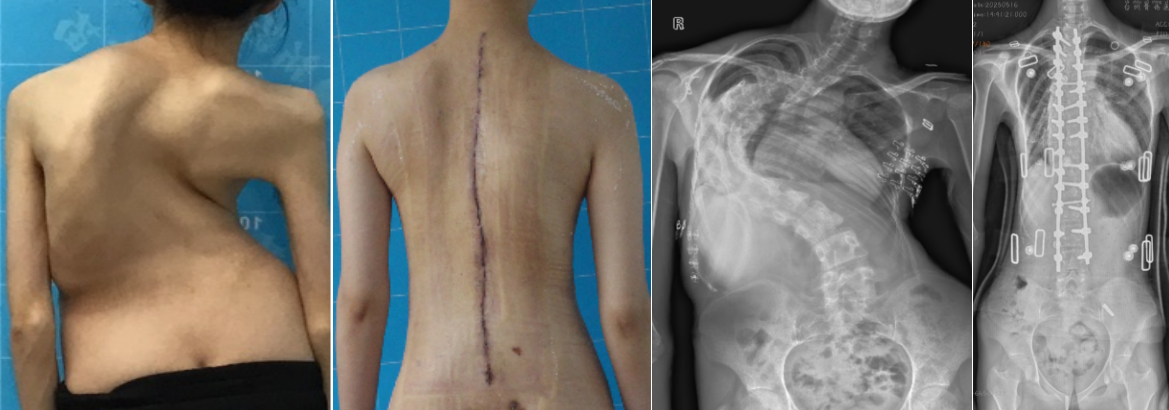

——这是23岁的小吴在术后康复期的真情流露。曾饱受极重度脊柱侧弯及严重肺功能障碍困扰的小吴,因病情复杂、手术高风险而四处求医未果。直至来到中山大学附属第三医院脊柱侧弯中心,命运迎来转折。

多学科专家团队为其量身定制“术前牵引+呼吸锻炼+营养支持+微创精准截骨矫形”的个体化治疗方案,在多学科的科学规划与国际先进术中导航指引和术中完善神经监护体系的护航下,手术顺利完成,不仅体态及心肺功能改善,患者亦重拾自信与笑容。